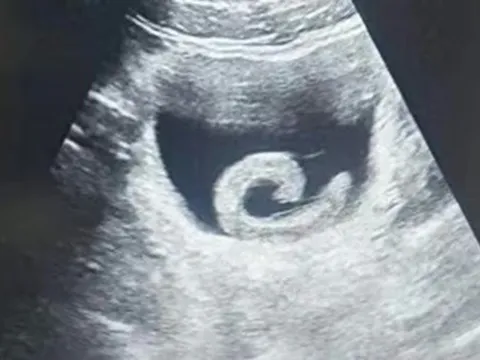

Nhịn ăn, uống chanh muối chữa ung thư, người đàn ông suy kiệt nghiêm trọng- Ảnh 1.

Mỗi sáng người đàn ông uống nước cốt một quả chanh pha muối để trị ung thư.